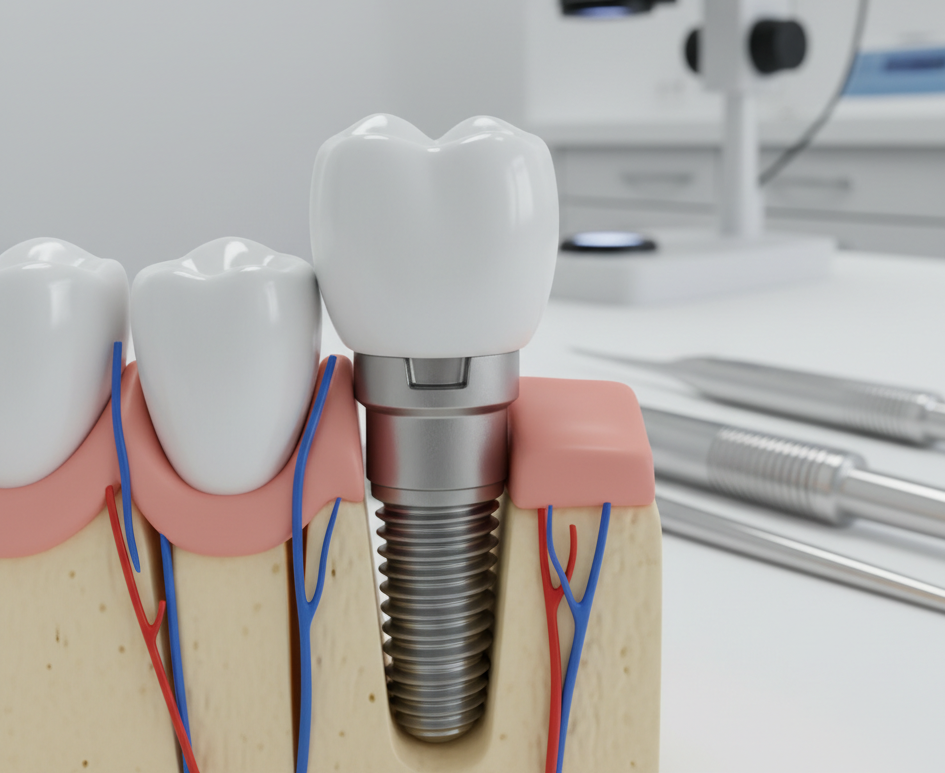

¿Es seguro un implante dental?

Ofrecemos servicios de prótesis, coronas e implantes dentales en David, Chiriquí, con un equipo especializado y un laboratorio dental digital propio para garantizar la calidad y tiempo de entrega de los tratamientos.

Ofrecemos servicios de odontología general, especialidades en restauraciones, coronas, potesis, implantes dentales y laboratorios dental digital, en David, Chiriquí

Planes de ortodoncia, protesis, coronas e implantes dentales, con atención integral.